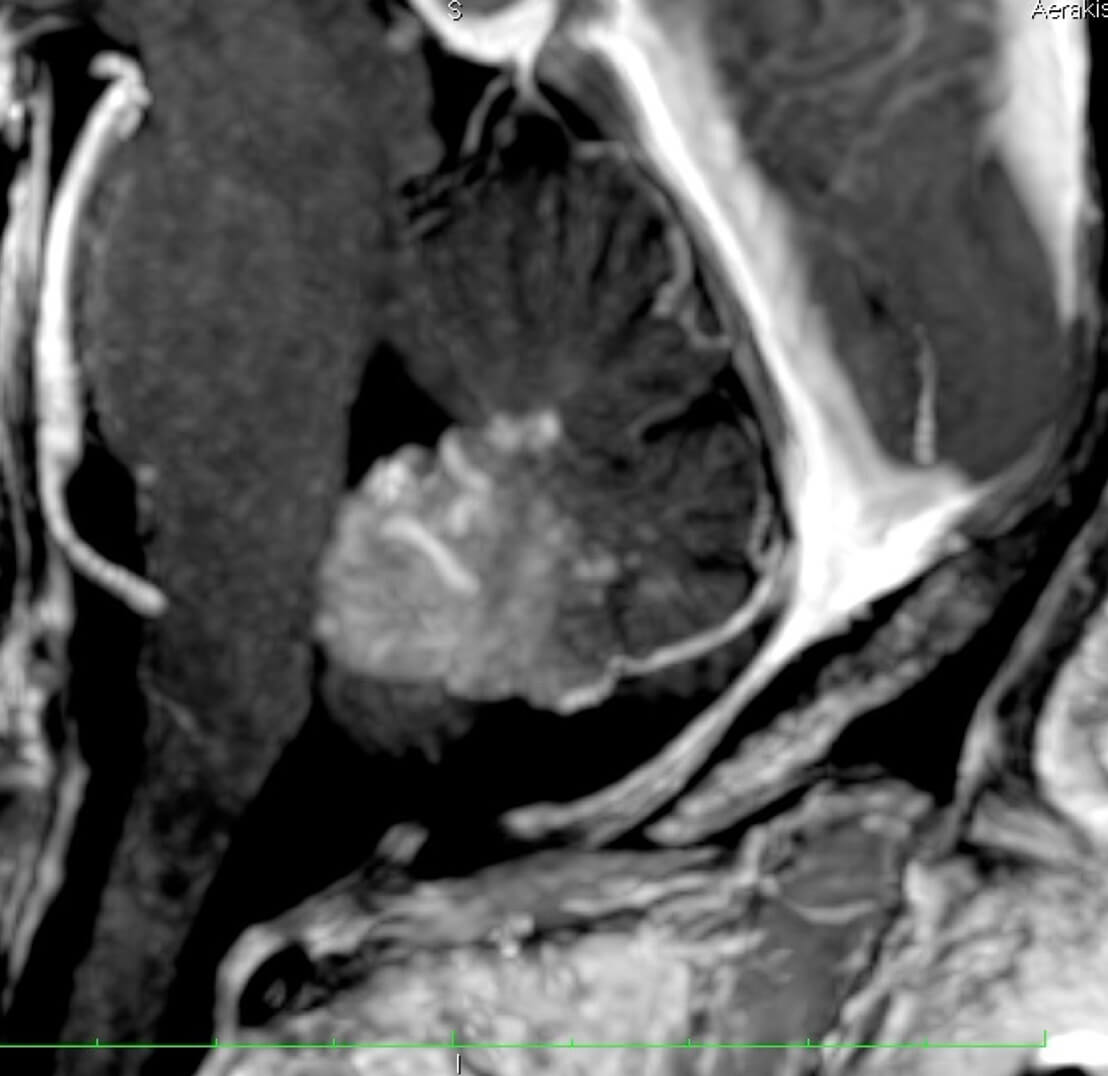

Σε επιθετικής μορφής μηνιγγικής ΑΦΔ με φλοιώδη παλινδρόμηση, ενδοκράνια αιμορραγία.

Μη αιμορραγικές νευρολογικές εκδηλώσεις όπως επιληψία, παρκινσονισμός, παρεγκεφαλιδική σημειολογία με αστάθεια.

Σε προχωρημένες καταστάσεις με μεγάλη εγκεφαλική φλεβική συμφόρηση, έκπτωση των ανωτέρων εγκεφαλικών λειτουργιών και άνοια.

Η αξονική αγγειογραφία έχει ελαττωμένη ευαισθησία έναντι της μαγνητικής αγγειογραφίας.

Παρ´ όλα αυτά η συμβατική ενδαρτηριακή αγγειογραφία είναι η πιό ακριβής γιά την αναγνώριση αλλά και την κατηγοριοποίηση των ΑΦΔ της σκληράς μήνιγγας.